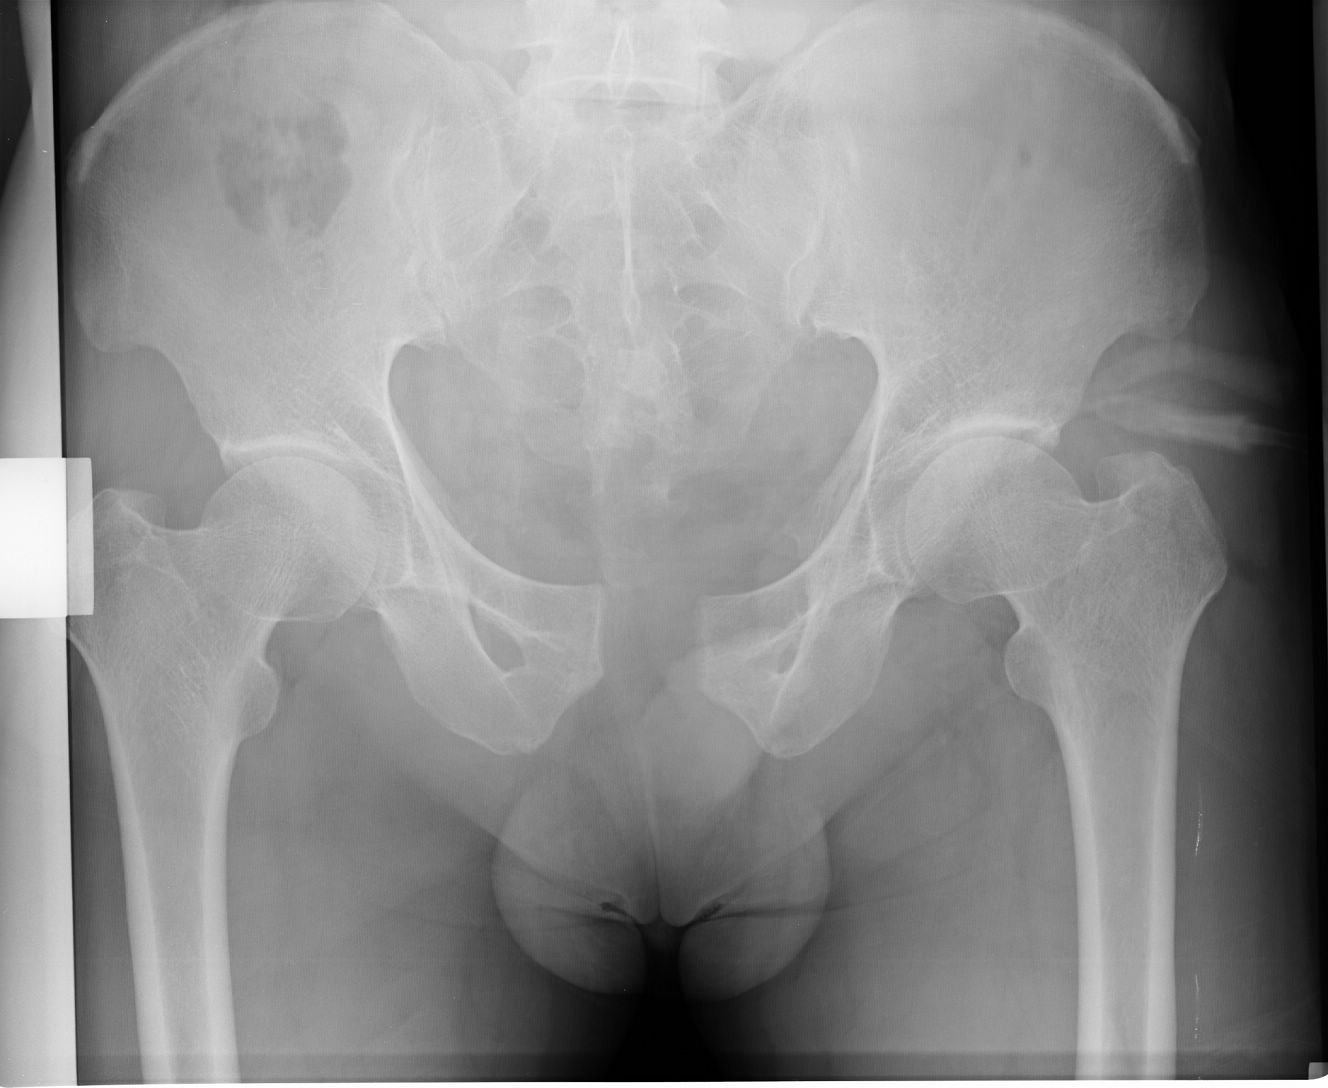

以下是引用liaoqiang在2008-9-2 15:27:00的发言:[br]耻骨联合分离。当心有尿道、膀胱损伤可能。

以下是引用杀毒软件在2008-9-2 17:20:00的发言:[br]支持 -------耻骨联合分离,骶骨近左侧耳状面骨折.

以下是引用随光逐影在2008-9-2 16:56:00的发言:[br]支持 耻骨联合分离,骶骨近左侧耳状面骨折并左侧骶髂关节分离。

以下是引用dyqct在2008-9-2 15:42:00的发言:[br]耻骨联合分离,左侧骶髂关节半脱位。建议ct进一步检查。